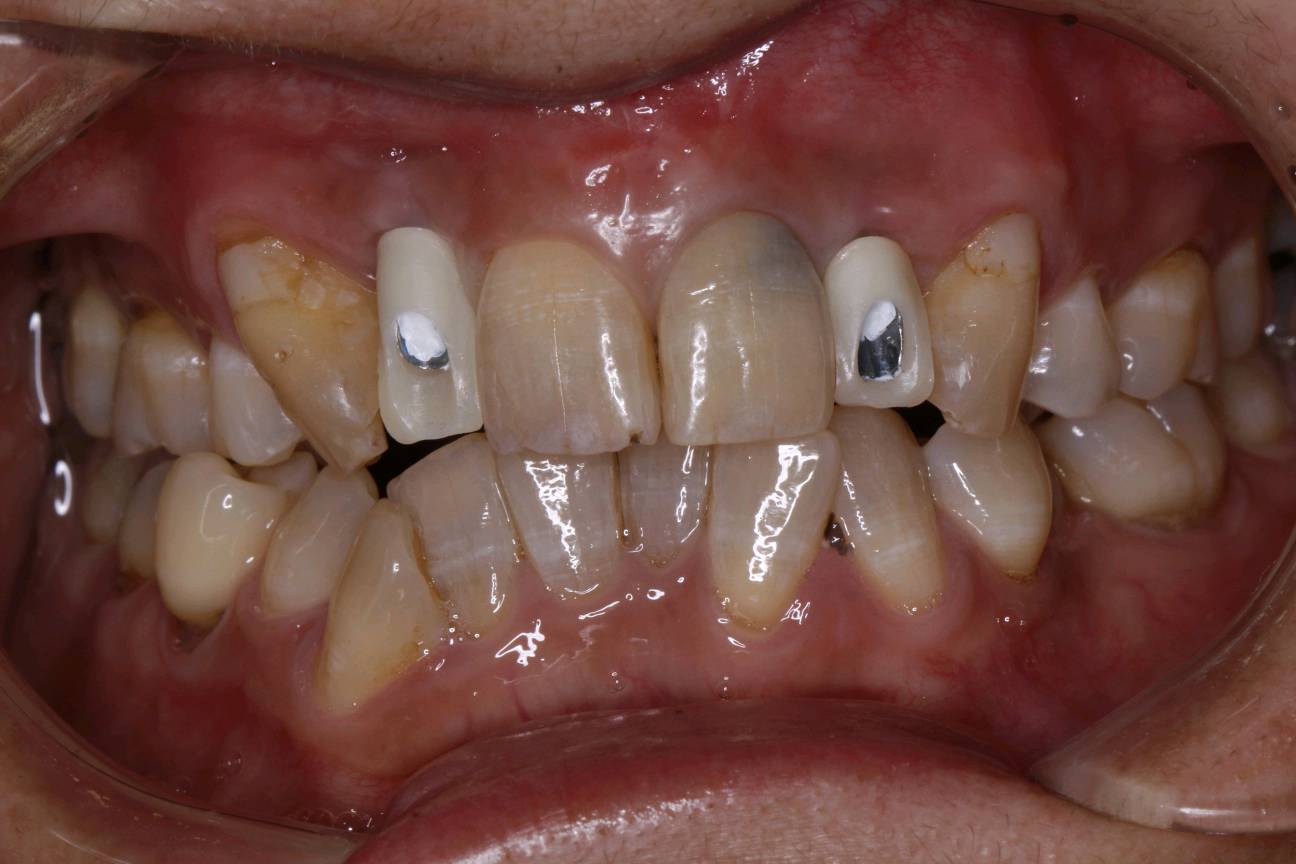

患者女40岁,12、22缺失,拔牙窝凹陷,牙龈乳头形态正常,近远中径较宽;唇侧龈缘曲线良好,与邻牙基本协调 。CBCT示:唇侧骨板不完整,牙长轴与上颌骨长轴平行。

术前